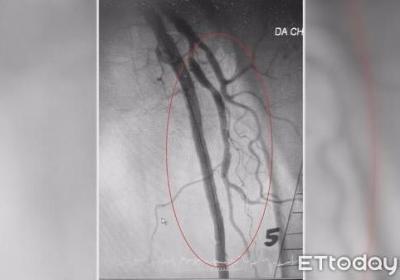

脚也会中风!3高患者腿部动脉易阻塞 小心溃烂、发黑要截肢,脚也会中风!3高患,者腿部动脉易阻塞 小,心溃烂、发黑要截肢...